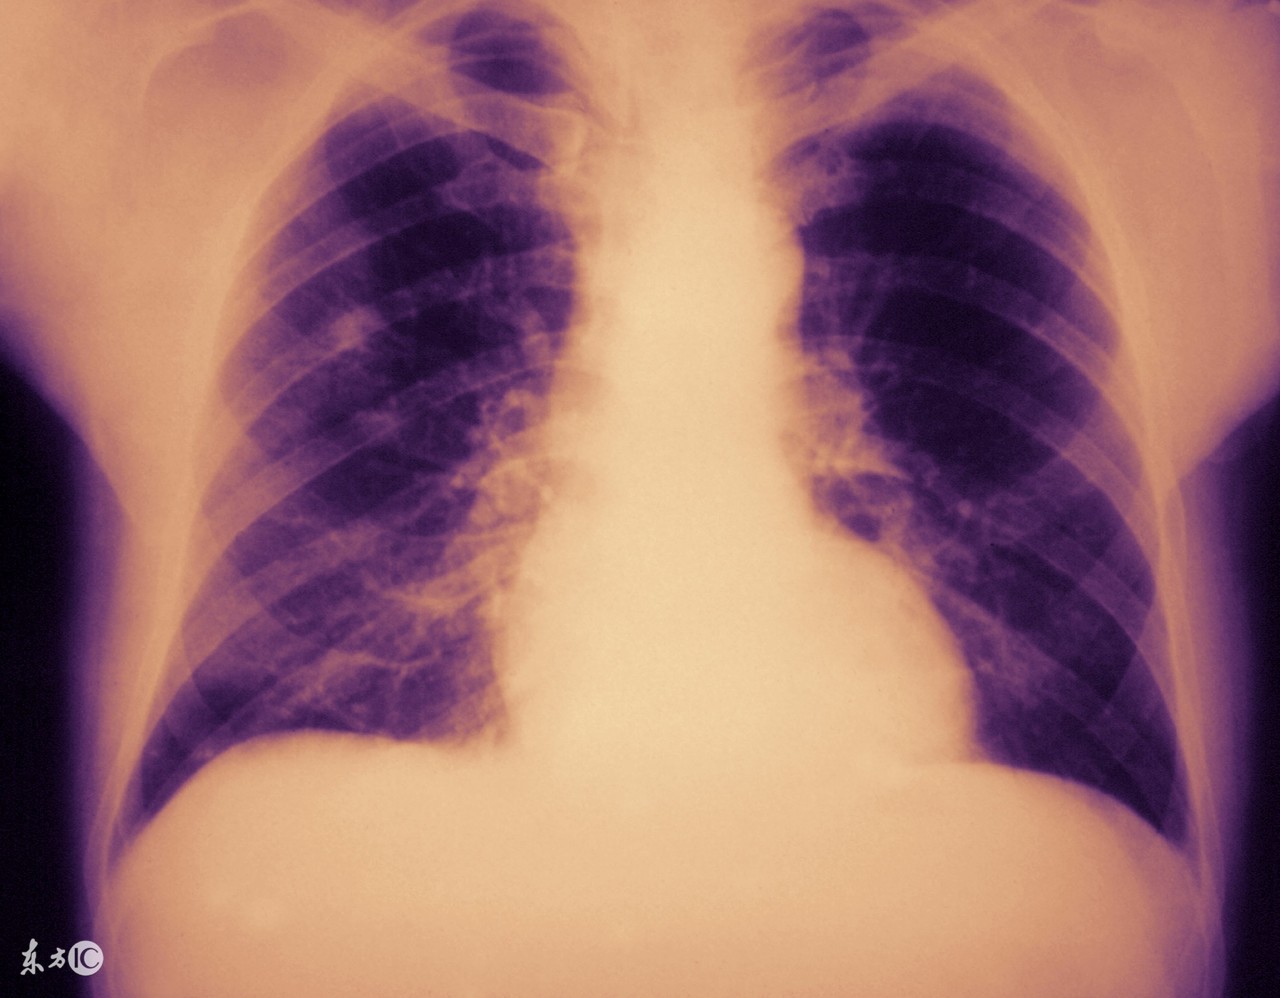

支原体肺炎其实也是肺炎的一种,但是这种肺炎不是因为细菌感染所导致的,既然如此,支原体肺炎具有传染性吗?如何预防?

支原体肺炎是一种冬季高发的传染病。由于其具有传染性,病人患病期间要注意隔离。而且支原体肺炎主要通过飞沫传播,除了能引起呼吸道病变外,还能引发心肌炎、肾炎、脑膜炎、血小板减少性紫癜等疾病。

而且支原体肺炎由口、鼻分泌物经空气传播,引起散发和小流行的呼吸道感染,主要见于儿童和青少年,现在发现在成人中亦非少见,秋冬季较多。呼吸道感染有咽炎和支气管炎,少数累及肺。支原体肺炎约占非细菌性肺炎的1/3以上,或各种肺炎的10%。因此预防支原体肺炎的措施有: